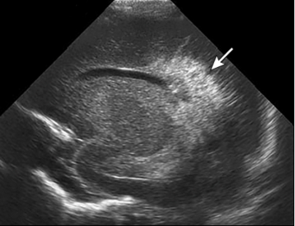

Neonatology PVHI Thalamus 2 Image